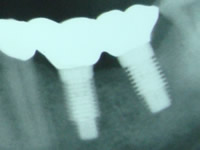

インプラント関連の機材

当院では、デンツプライ社製アストラテックEV・プライムテーパー、ストローマン社製BLT、バイオホライゾンを症例に応じて使用しています。